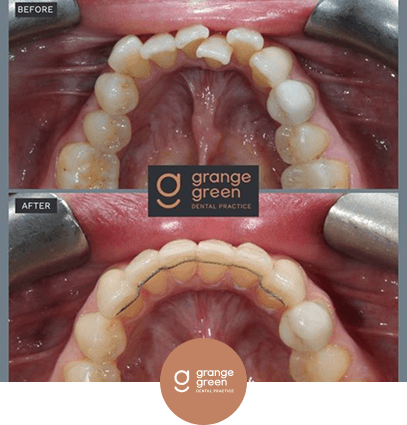

Here are just a few before and after cases to give you an idea of how we help to transform your smile and your confidence using treatments like orthodontics, bridges, veneers and composite fillings…